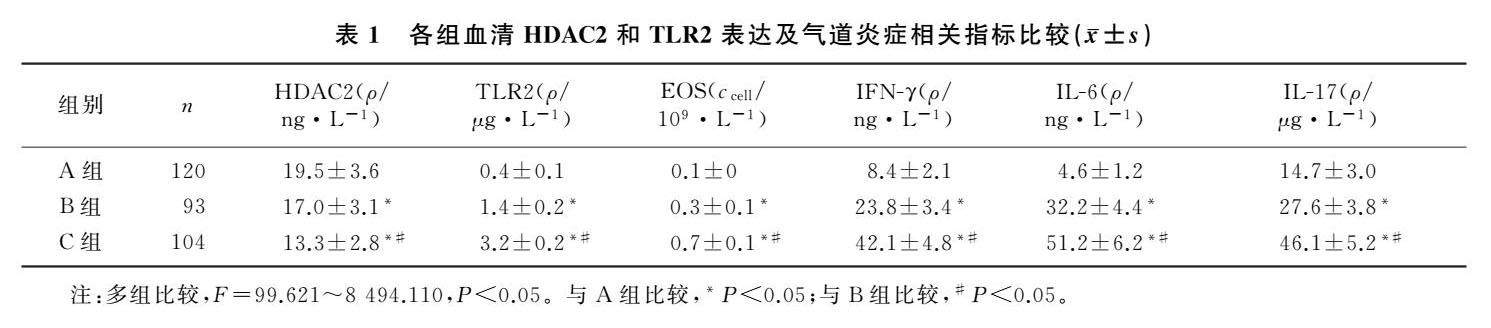

论著 | 咳嗽变异性哮喘急性发作病儿血清HDAC2和TLR2检测及意义

论著 | 咳嗽变异性哮喘急性发作病儿血清HDAC2和TLR2检测及意义